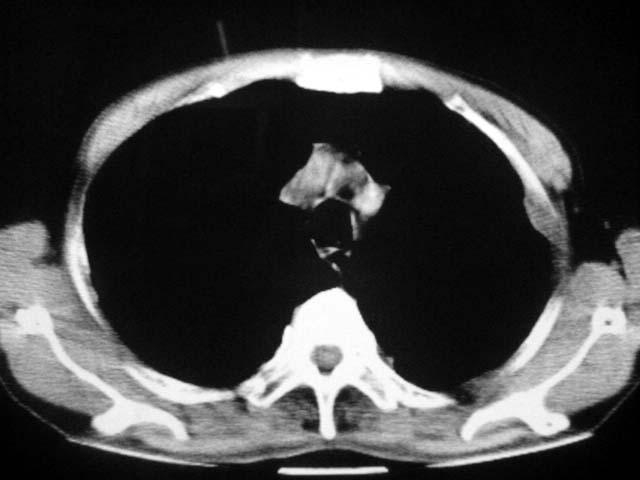

以下是引用zjzjr在2007-9-4 17:00:00的发言:[br]双上肺继发型结核伴左上肺空洞形成.慢性支气管炎伴肺气肿.

以下是引用liuzheng_9326在2007-9-4 16:23:00的发言:[br]痰检未见结核菌, 治疗后症状好转。图像符合陈旧性结核伴感染。